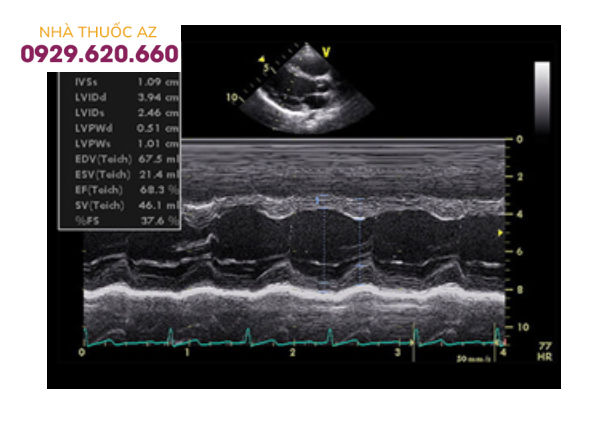

Siêu âm kiểu TM

Siêu âm tim kiểu TM, lát cắt trục dọc cạnh ức trái, cursor ỏ sát đầu tận cùng van hai lá, đo được đường kính thất trái cuối tâm trương (LVIDd), đường kính thất trái cuối tâm thu (LVIDs), qua đó tính chức năng tâm thu thất trái (EF). Ngoài ra còn đo được kích thước thất phải, độ dày của thành thất trái ở tâm trương (IVSd và LVPWd) và tâm thu (IVSs và LVPWs).